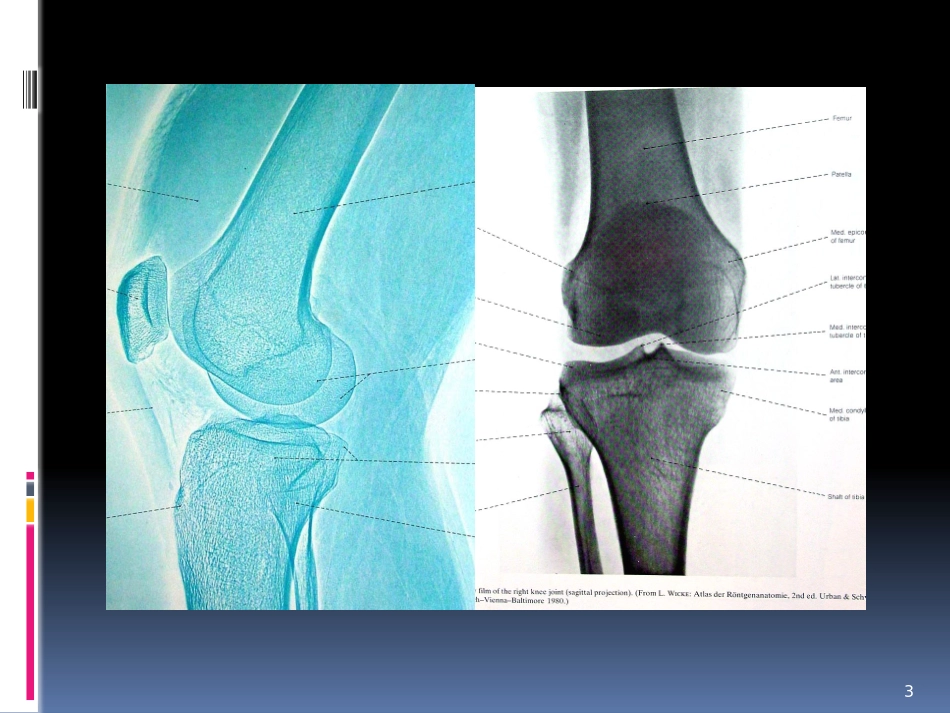

膝关节的功能锻炼方健辉解剖345膝关节滑膜结构特点1、滑膜面积最大,分泌区广;2、脂肪垫最大、绒毛数目最多;3、能适应膝关节的功能(运动、产热、负重);4、与周围结构分隔,邻近区域的病变不易蔓延到关节内。6膝关节韧带髌韧带patellarligament髌内侧支持带髌外侧支持带伸膝装置髌韧带髌内、外侧支持带股四头肌腱髌骨7外侧支持带髌韧带内侧支持带膝关节的韧带胫侧副韧带tibialcollateralligament股骨收肌结节胫骨内侧髁内侧腓侧副韧带Fibularcollateralligament股骨外上髁腓骨小头下方8腓侧副韧带胫侧副韧带膝关节的韧带前交叉韧带髁间隆起前部内、外半月板前角后交叉韧带髁间隆起后部外侧半月板后角9股骨外侧髁内侧股骨内髁外侧前交叉韧带后交叉韧带膝关节半月板附着关节囊内面,外缘厚、内缘薄。外侧半月板呈“O”形、内侧半月板呈“C”形。10功能:1、吸收震荡、缓冲冲击力。2、楔形形成浅窝、稳定膝关节。防止关节囊嵌入。3、协助控制膝关节运动。4、使关节滑液均匀分布5、负重功能内侧半月板外侧半月板膝关节运动屈伸运动为主、并可有限度旋转运动。1、运动轴不固定2、滚动与滑动3、旋转活动旋内为10º旋外30-40º4、扣锁机制膝关节伸至160-180º,每增加伸直1º时,股骨约内旋0.5º。11运动学常见膝关节运动损伤的功能锻炼髌骨劳损前十字韧带重建术后骨性关节炎练什么怎么练练什么关节活动度力量:耐力、速度耐力、爆发力、最大力量本体感觉平衡、灵活怎么练1、明确诊断2、选择合适的方法、工具(自行车、TRX)3、避免疼痛4、单足训练5、全身训练力量锻炼的几个注意问题选择目标选择合适的训练区域每个肌群的训练组数每个肌群合适的训练动作数量合适的训练动作合适的训练动作顺序间隔时间恢复功率自行车靠墙单足蹲TRX半蹲走跑台跑